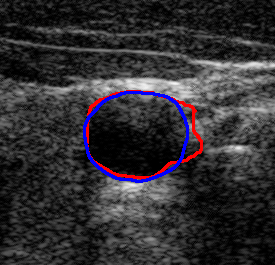

4.7 Downstream Task on Ultrasound Image Segmentation

To showcase the potential of the proposed denoising method quantitatively for ultrasound image understanding, we evaluate its impact on carotid ultrasound segmentation as a downstream task [9]. In this task, we use unseen noisy carotid images collected from the Clarius device. Then, unsupervised Segment Anything 2 (SAM2) [66] and the rule-based Flood Fill algorithm are used to extract the carotid artery from noisy and denoised images processed by various despeckling algorithms. In both cases, we place the seed point at the geometric center of the carotid lumen in each frame.

The quantitative result in terms of both IoU and AUC has been summarized in Table 6. To provide an intuitive visualization of the comparison, the results of SAM2 on a representative image and its denoised variants are presented in Fig. 12. It can be seen from Table 6 that the overall results using SAM2 are significantly improved in comparison to the Folld fill algorithm. This is primarily because of the strong generalization capability of the foundation model itself. Although the results produced by SAM2 across different images are comparable, the outcomes on images denoised by our method consistently demonstrate superior performance. The AUC reaches the highest score among all methods, while the IoU achieves the second-best performance. This performance advantage becomes more pronounced when using traditional region-growing algorithms such as the Flood Fill method. Significant improvements in both AUC ( vs ) and IoU ( vs ) are observed when applying the proposed Speckle2Self denoising approach.